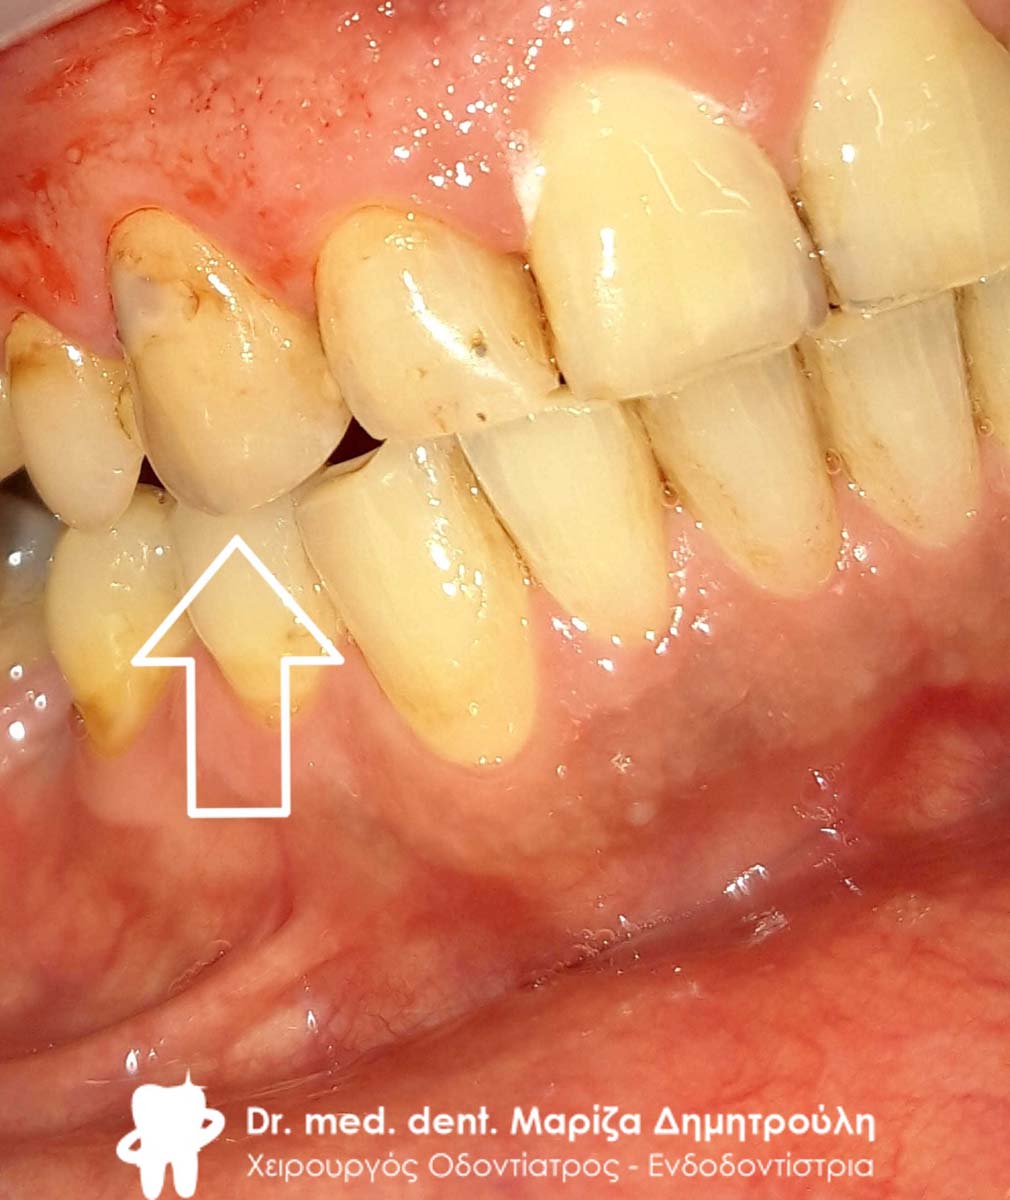

Ο ασθενής επισκέφτηκε το ιατρείο με σκοπό την αλλαγή ενός παλιού λευκού σφραγίσματος που υπήρχε στον αριστερό κυνόδοντα της άνω γνάθου. Το συγκεκριμένο δόντι τον ενοχλούσε τόσο αισθητικά, καθώς παρουσίαζε δυσχρωμίες όσο και λειτουργικά, γιατί πολλές φορές τον ενοχλούσε κατά τη μάσηση.

Μετά την κλινική εξέταση διαπιστώθηκε οτι το συγκεκριμένο δόντι είχε επανατερηδονιστεί. Η θεραπεία επιλογής ήταν η αφαίρεση του παλιού δυχρωμικού παλιού λευκού σφραγίσματος και η αντικατάσταση του με νέο λευκό σφράγισμα ρητίνης.

ΠΡΙΝ

META